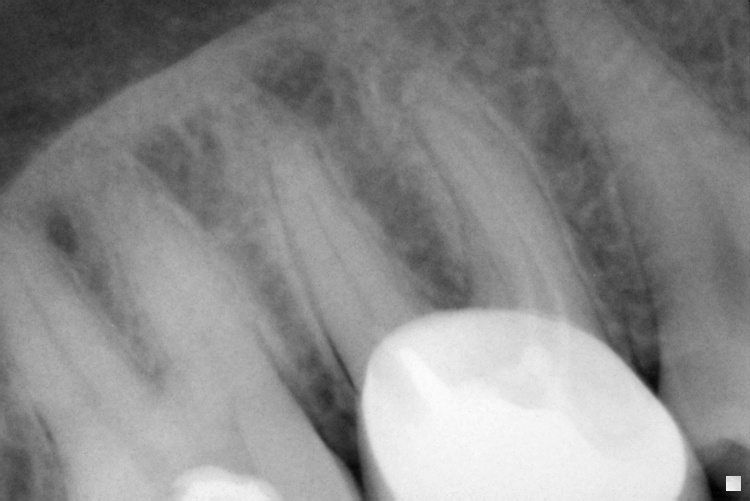

Name Last modified Size Description Parent Directory - IO000001.jpg 2020-07-28 13:55 84K IO000002.jpg 2020-07-28 13:55 68K IO000003.jpg 2020-07-28 13:55 83K IO000004.jpg 2020-07-28 13:55 92K